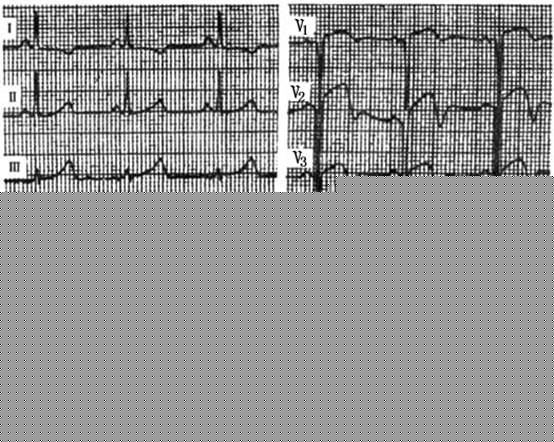

(3)急性心肌梗死心电图演变:心肌梗死的心电图演变的过程(图1)通常分为4期,即超急性期、急性期、亚急性期及陈旧性期。

①超急性期:发生在发病后的数分钟至数小时,是急性心肌梗死最早期阶段。此期由于冠状动脉急性供血不足,心肌尚未坏死,处于可逆阶段,心电图尚未有异常Q波。但此期电活动极不稳定,易发生室性期前收缩、室性心动过速,甚至室颤。典型的心电图改变表现为T波高尖、ST段损伤型抬高、急性损伤阻滞。 医学百科网 | YxBaike.Com

②急性期:心肌梗死急性期开始于发病后的数小时或数天,可持续数天至数周。它的心电图可表现为心肌坏死、损伤和缺血的特征同时存在,反映了心电图从超急性期以损伤为主的状态,转变为以缺血与坏死为主的状态。急性期原发性室颤的发生率较超急性期减低。

③亚急性期:发生在发病后的数周到数月。此期的心电图以坏死与缺血图形为主要特征。 医学百科网 | YxBaike.Com

④陈旧期:发生在心肌梗死后数月至数年。通常在心肌梗死发病的6~8周后,坏死的心肌组织已被瘢痕组织取代,缺血消失或固定存在。此期反映了从急性期最大限度的恢复。通常非透壁性急性心肌梗死恢复后,心电图多可完全恢复正常。但是,绝大多数的透壁性心肌梗死恢复后都会在心电图上遗留有异常的改变,即异常Q波。陈旧期心肌梗死心电图的主要特征如下: